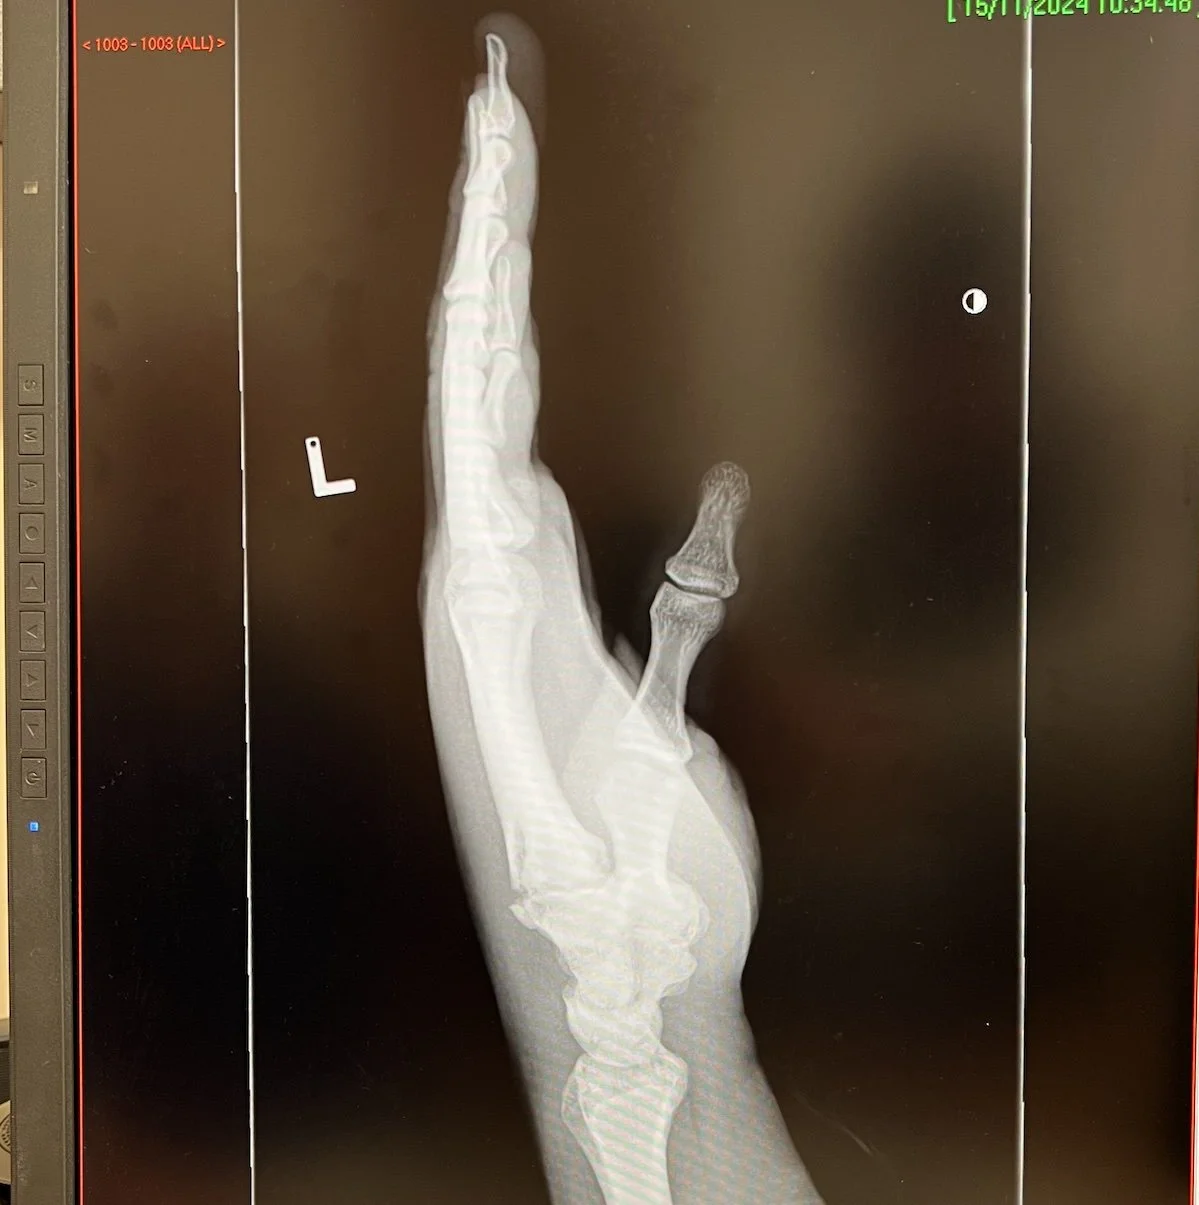

The following weekend I was off to Glasgow for the Tea Green Events Christmas Market at The Burrell Collection. Last year, this market had 10,000 visitors over the weekend so I was excited to see how it would go. I stayed with a friend over the weekend which kept costs down for accommodation. A few days before the market I fell off my bike and landed awkwardly on my hand. I later found out I had broken at least 1 metacarpal after an x-ray (pictured below). This made setting up very slow and painful - top tip, don’t injure yourself before one of the biggest events of the year…